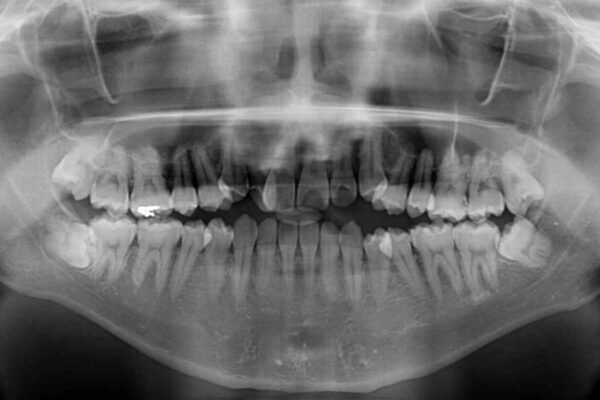

八重歯と前歯のデコボコを気にして来院された患者様です。

治療計画

営業職であり、商談などで飲食をする機会が多いとのことで、インビザラインではなく、ワイヤー装置にて矯正治療を行うこととしました。

舌の突出癖がなかなか改善されず、上下前歯部の接触が得られるまでに予定の倍ほどの期間がかかりました。